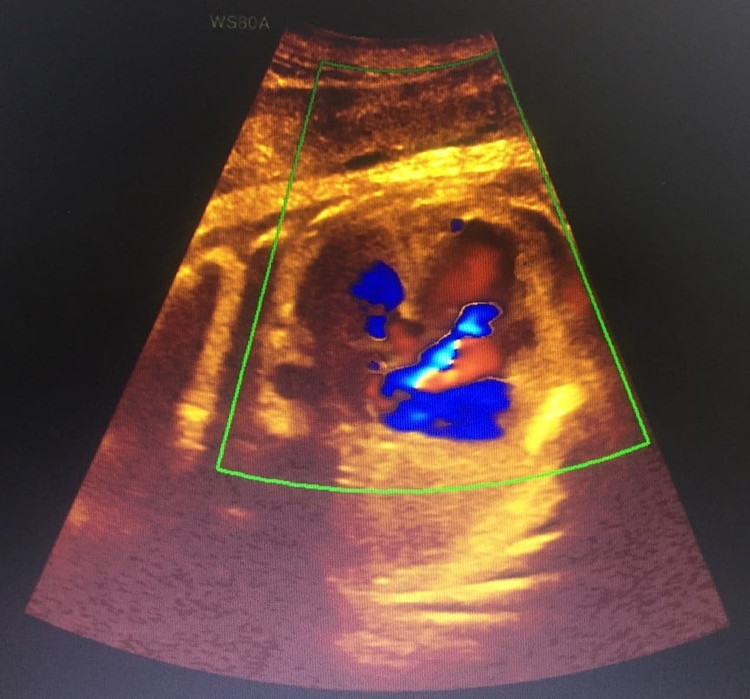

Kết quả siêu âm: Thai 39 tuần - Kênh nhĩ thất bán phần, hở van 3 lá, tràn dịch màng ngoài tim, thai chậm tăng trưởng trong tử cung, cạn ối.

| Hình ảnh siêu âm phát hiện ra bất thường của bệnh nhân |